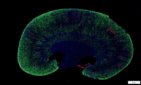

Immunofluorescence, IF

IF螢光染色